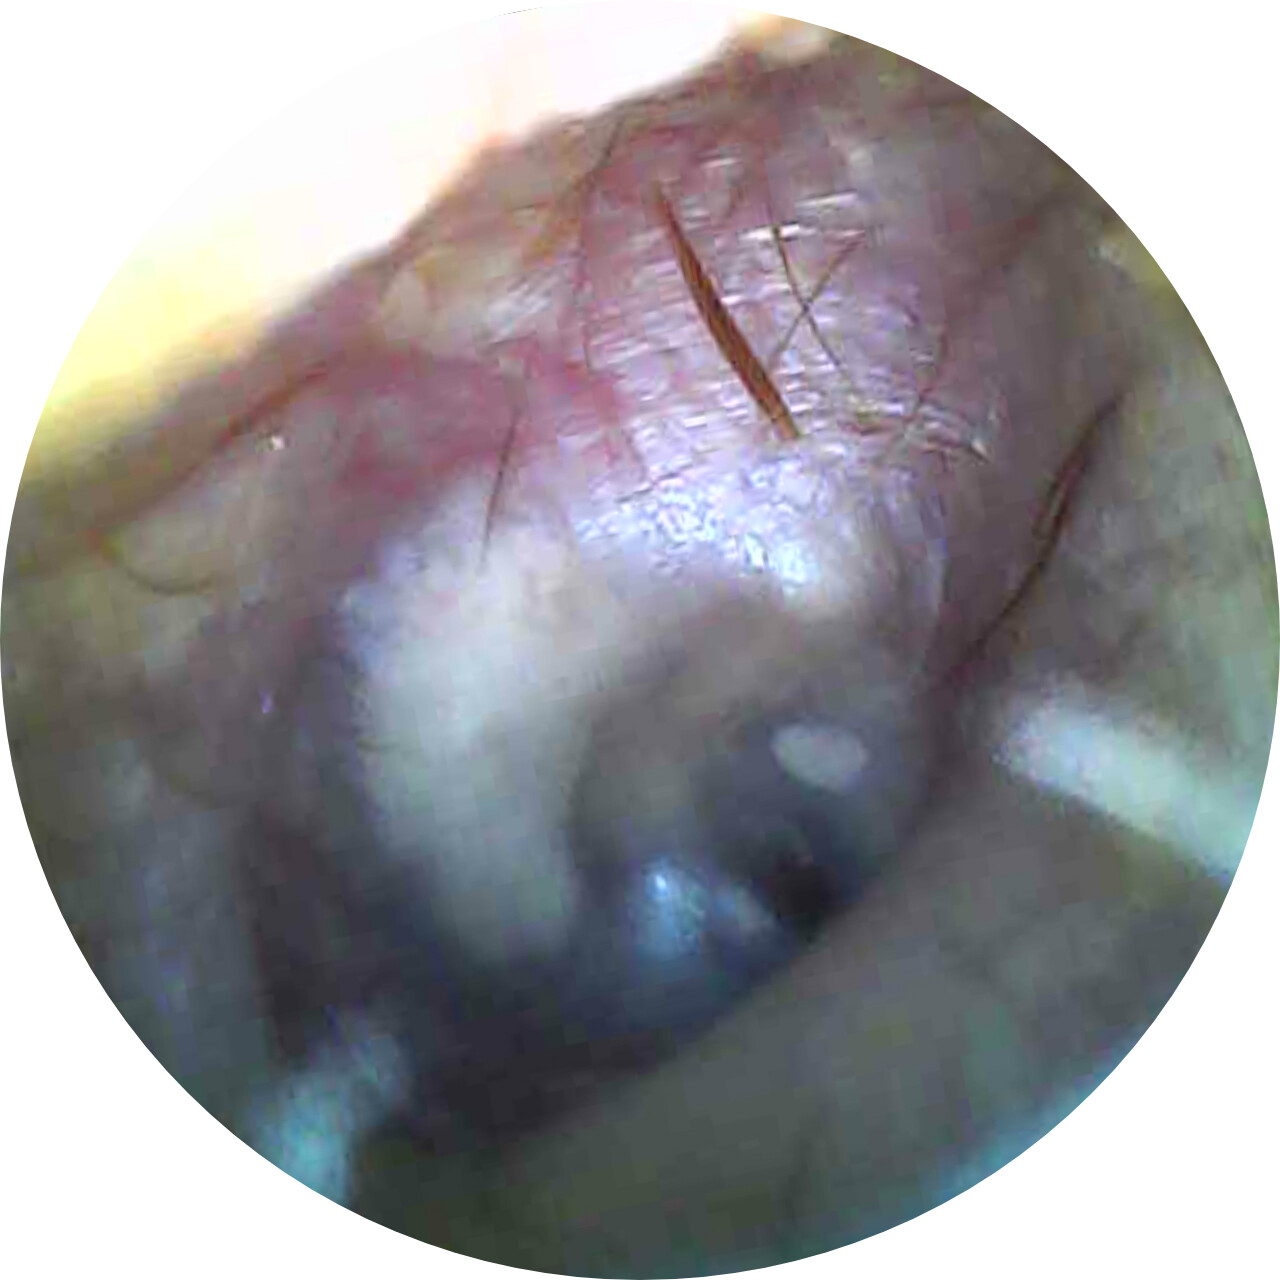

Below are some screenshots from my Cone Beam CT scan and the report linking possible ES. I have more Regular CT scans I could possibly share and/or if you would like me to get possible better angles from the Cone Beam CT scan let me know. But as of right now I’m at a loss as what to do going forward. I do have an MRI with and without contrast of the Cervical Spine Scheduled, but that’s due to the doctor’s (the doctor that dismissed it as ES and one doctor that wants to follow up and learn more on it) wanting it.

- Now onto this year, I finally got better back to full health in late November early December 2024 and sadly started to get another sinus infect in January and still no answers to why. I just happen to be watching YouTube when a Dentist had said that your teeth could be linked to sinus issues causing sinus infections and normally the only way to tell if this is the case is to get a Cone Beam CT scan. I then thought this could be another lead to find out why I keep getting sick as I did when I was 10 have my first top premolar on my left side removed against what I wanted as they said my teeth were too crowded and it needed to be removed so I could have braces (which that dentist didn’t even do my braces anyway). But I thought when he removed it if a small piece of the root was still in there as he just broke out the tooth without removing it via surgical means that that could cause an abscess in my Left Maxillary Sinus where infections always start. So, finally I was able to find a place that would give me a Cone Beam CT scan back in February of this year all while I was just starting to get sick from my infection. Anyway, I finally got the report in March and found out oddly my Left side is mostly normal other than mucus polyps, but I have a few other issues (I have attached the report below). This report is where I first found out about Eagle Syndrome as it states I might have Calcified Ligaments and further testing is needed to confirm. It was only after this report and looking up what Eagle Syndrome was that I can say I have almost every symptom that has ever been reported. Sadly, I couldn’t find anyone in my State at the time that work with Eagle Syndrome and when I did was about a week before I found this site and the doctor I did see seemed to dismiss me as another hypochondriac and you can’t have it as you don’t have Vertigo type Dizziness, my styloid are normal length and I don’t have neck pain equivalent to having to be in a neck brace. Not only this she only looked at my CT scan from a week earlier that I had got in Emergency. The Emergency visit was due to the fact at 8PM that night I had pain in my Right Mastoid Bone, and I was starting to get an earache. I went to lay down and took pain meds and an ice pack in hopes to reduce the pain and swelling. I couldn’t sleep due to the pain and came upfront about 10PM. 10:21PM I couldn’t take it anymore and started to stretch my neck and I felt a huge snap and heard a load pop, all the pain just felt like it disappeared. One minute later, I had a massive pain that spread just like when you get an IV that stings, but it felt like someone was trying to murder me and stabbed a knife into the right side of my skull. I was in so much pain that I was hunched over, and we had to have an ambulance called. I thought I was having an aneurism and my mother thought I was having a Stroke (very rare ES Symptom). When the ambulance arrived, they took my vitals, and my blood pressure was 148/110 with a pulse in the high 90’s low 100’s. Luckily the pain had subsided enough that we were able to go to emergency without the ambulance ride, but while I was in emergency the pain had spread to my left side of my head and now felt like someone had taken a clothes iron and stuck it on my head. Any breeze moving my hair was pure agony and I couldn’t lay my head on a pillow without that burning pain. According to emergency though I must have just had a Mastoid Process infection and it burst. Luckily the pain went away by the time I went to the Doctor for ES, but like I said before they were of no help.